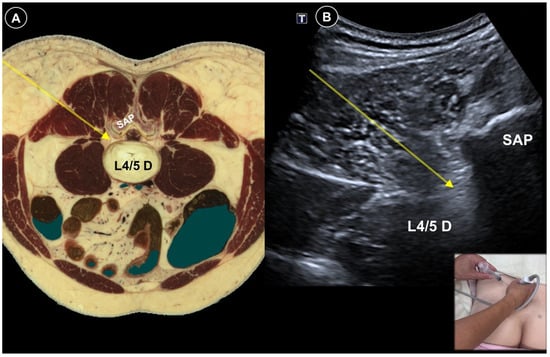

| Painful radiculopathy | Pain, numbness, clumsiness and even weakness in the distribution of the affected nerve root | Mechanical compression and inflammatory irritation of the nerve root, often due to disc herniation or spondylosis | Cervical: supine, head turned to contralateral side Lumbar: prone | Cervical: linear, in-plane

| Improvement of pain by ESI (meta-analysis), SNRB/caudal block (RCT) |

|